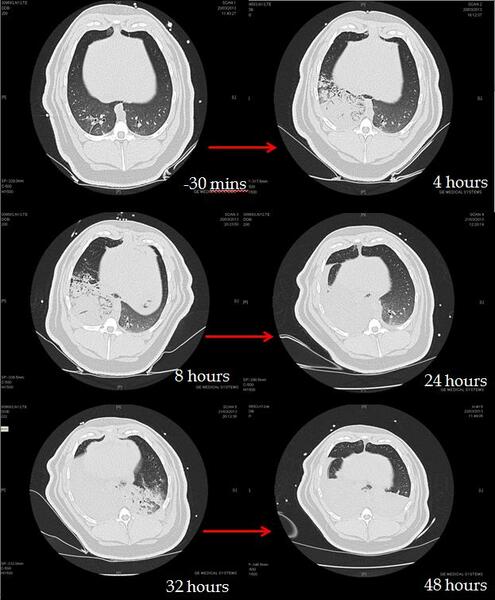

CT analysis of an OP and GJ pig lungs show the direct and indirect effects of aspiration over time (figure 2).

Figure 2: Time series CT lung scans taken from one pig at -30 minutes (before aspiration) to 48 hours after instillation of 0.5mls/kg mixture of OP and gastric juice in the right lung at time 0 hours. Over time, the right lung becomes more consolidated and at 32 hours the left lung also starts to show an indirect injury. At 48 hours bilateral posterior consolidation and fluid in the fissures are apparent.